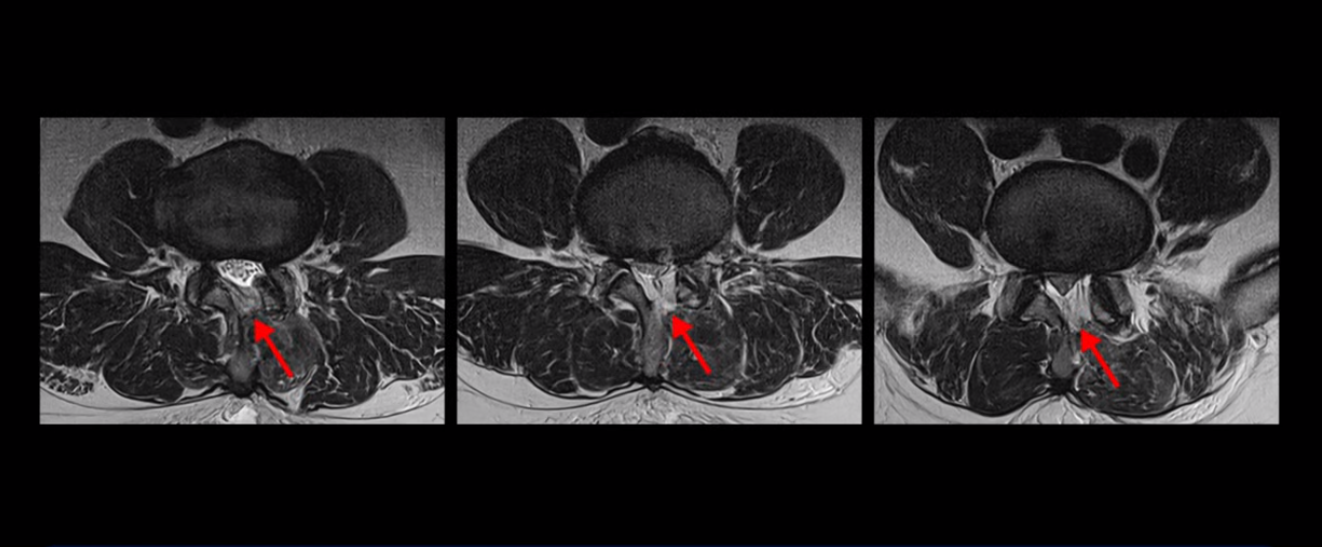

목 5번 6번을 보면 디스크가 심하게 밀려 나와서 척수 신경을 누르고 있습니다.

척수 신경이 눌려서 손상된 사인이 하얗게 보입니다. 이걸 경추척수증이라고 합니다.

척수 신경이 눌리고 손상되니까 양쪽 손과 양쪽 다리 모두에 증상이 생깁니다. 양손에 힘이 빠지고 젓가락질이 힘들고, 단추 끼우기도 어려워지고 다리에 힘이 빠지니까 걷기도 힘들어집니다. 양손과 다리의 감각도 떨어지고요. 그래서 이 환자분은 수술하더라도 목 수술을 해야 하는데, 엉뚱하게도 허리 수술을 받습니다. 처음에 병원에 갈 때 허리도 원래 많이 아팠다고 하니까 그 병원에서 목 검사와 허리를 함께 검사해 보고 허리 협착도 심하니까 허리 수술을 먼저 하자고 합니다. 그래서 허리 세 마디를 수술했습니다.